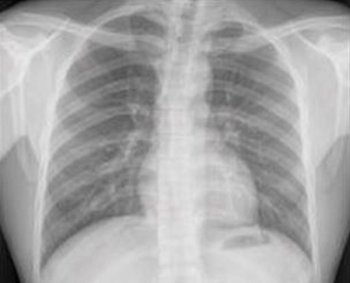

Based on a single existing chest X-ray image, the deep learning model predicts future major adverse cardiovascular events with similar performance to an established risk scoring system and may help identify people for preventive use of statin medication.